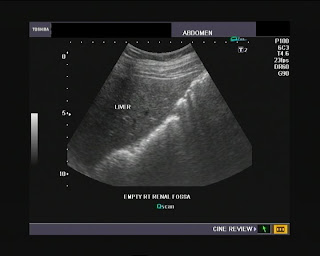

Abdominal And pelvic ultrasound Scan

Abdominal and pelvic ultrasound scan You are attending hospital for an ultrasound scan of your upper and lower abdomen (stomach). A doctor or sonographer will carry out the examination. The examination takes about ten to 20 minutes and we ... Retrieve Document